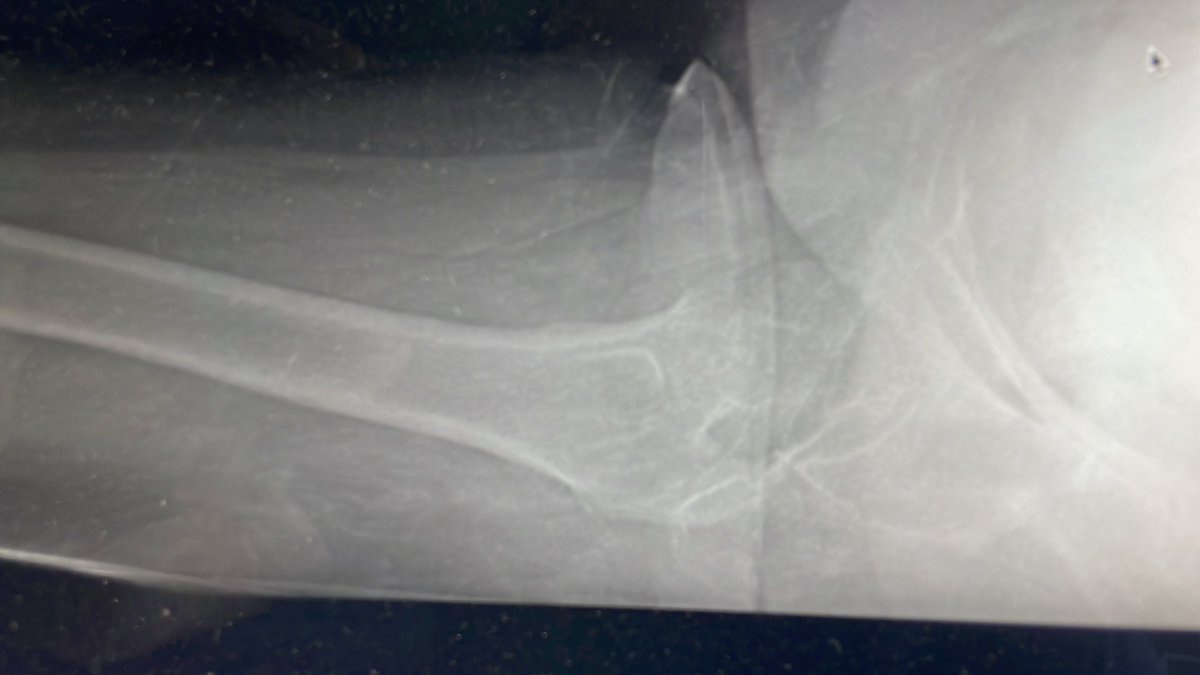

85 yo F. Healthy and active. Lives at home and walks with no aid. Knocked over by an animal and has this femoral neck fracture.

What do you do? @drsebheaven @BrianChalmersMD @FixnBones @jointdocShields @DrMarecek @CE_HandSurg @drs462 @CenterRotation @rkh_md @ExeterHipUnit